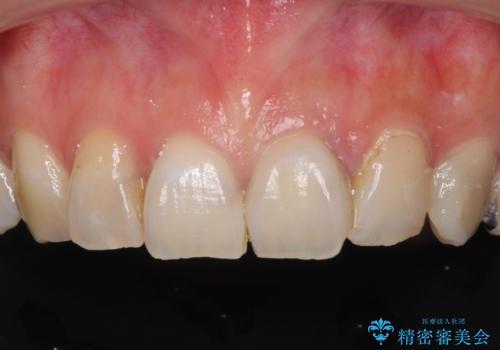

大きなむし歯と欠損をセラミックに 部分矯正を併用した総合歯科治療

- 長年むし歯を放置してしまっているとのことで来院された患者様です。

神経が除去されている歯、根管治療の必要な歯、むし歯の非常に大きな歯に対してオールセラミッククラウンにて補綴治療を行うこととしました。

途中通院されなかった時期が何度かあったため、初診から4年以上の年月がかかりましたが、比較的スムーズに治療を進めることができました。

下顎前歯の歯列を整えたことで、上顎前歯の咬み合わせが安定し、自然な口元に仕上げることができました。